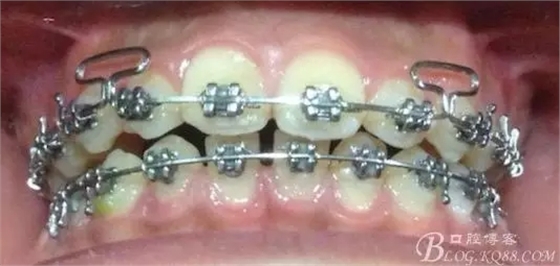

看看口內照吧!真象“大暴牙”v假象“大暴牙”

三度深覆合,三度深覆蓋,尖牙,磨牙均二類關系!